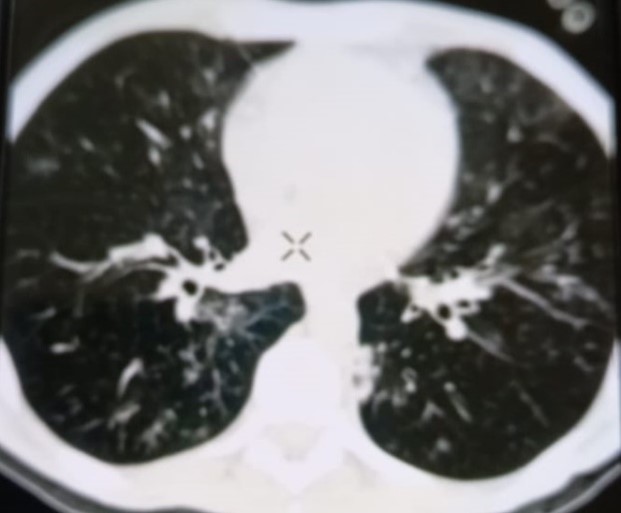

При проведении рентгенологического исследования органов дыхания в динамике спустя 2 недели с момента начала терапии данные компьютерной томографии высокого разрешения указали на следующие изменения: на фоне очаговой диссеминации в легких значительно увеличились по площади участки "матового стекла" в верхних долях обоих легких (описанные зоны неоднородные, сливные); площадь поражения легочной ткани - около 35-40%. В средних и нижних отделах легких с двух сторон выявлялись многочисленные перибронхиальные очаги до 3 мм в диаметре по типу «дерево в почках». В S 6 справа определялась зона альвеолярной инфильтрации. Выпот в плевральных полостях не определялся; внутригрудные лимфоузлы не увеличены. Заключение: признаки двусторонних полисегментарных интерстициально-инфильтративных, диссеминированных мелкоочаговых изменений легких, средняя вероятность вирусной пневмонии (в том числе COVID-19), в сочетании с диссеминированным процессом в легких (рис. 1-4).

Рисунок 1

Рисунок 2

Рисунок 3

Рисунок 4

Рис. 1-4. Компьютерная томограмма пациента Т., с ВИЧ: чередование участков «матового стекла» с диссеминированным процессом, инфильтрацией легочной ткани справа, наличие симптома «дерево в почках» (респираторный бронхиолит).

Учитывая на подозрительные в отношении туберкулеза легких КТ-признаки, пациенту впервые проведена метод ПЦР-диагностики выявления ДНК микобактерий туберкулеза, который показал положительный результат, что позволило установить диагноз «Диссеминированный туберкулез легких, двусторонний. КУМ «-» в сочетании с коронавирусной инфекцией COVID-19 средней степени тяжести, пневмоцистной пневмонией и бактериальной пневмонией» у пациента с ВИЧ-инфекцией 4В стадии. Для дальнейшей терапии пациент был переведен в стационар туберкулезного профиля.